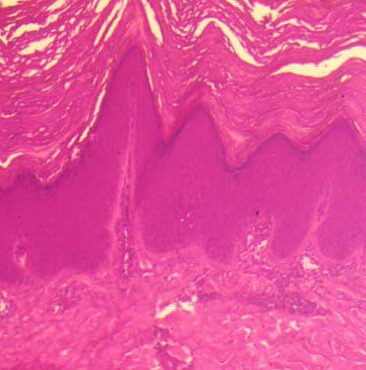

Erythema elevatum diutinum = الحمامى المرتفعة الدائمة Erythema Elevatum Diutinum This rare condition is characterized by persistent, initially red to violaceous and later brown to yellow papules, nodules, and plaques . The lesions, typically distributed symmetrically on the extensor surfaces of the extremities, are initially soft and then evolve into fibrous nodules. Histopathologic Features. In […]